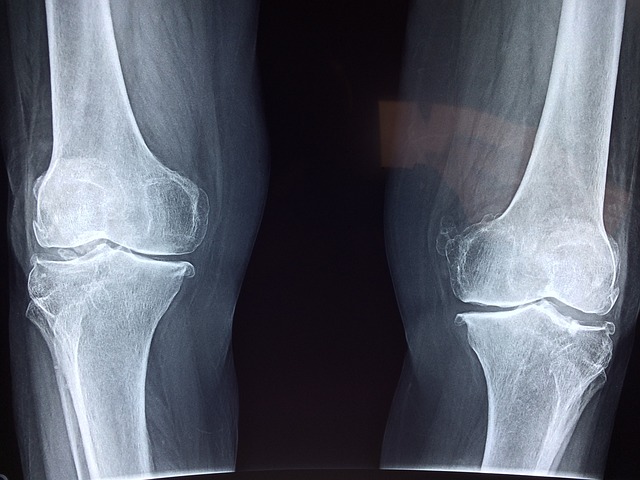

4-1 골관절염 관절 통증 치료에 도움

퇴행성관절염은 우리가 피해갈 수 없는 질환입니다. 앞서 말씀드렸다시피 움직이지 않고 가만히 있지 않는 이상 관절은 계속 닳고 있습니다.

콘드로이친은 얇고 닳기 쉬운 연골의 마모를 방지하고 연골의 부피 유지에 기여하여 관절염의 통증을 완화하는 데 도움을 줄 수 있습니다.

한 연구에 따르면 무릎 통증 환자를 대상으로 콘드로이친을 4개월간 섭취하게 한 결과 관절 통증이 43% 감소하고 보행 능력이 개선되었다. 섭취 후 6개월 뒤에는 관절의 경직 시간이 줄어든 것으로 나타났습니다.

또 다른 연구에서는 무릎 퇴행성 관절염 환자 622명 중 콘드로이친 황산을 섭취한 사람들의 관절염이 줄어들고 관절 사이의 간격이 넓어졌다고 합니다.